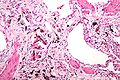

Ferruginous bodies. H&E stain.

A ferruginous body is a histopathologic finding in interstitial lung disease suggestive of significant asbestos exposure (asbestosis). Asbestos exposure is associated with occupations such as shipbuilding, roofing, plumbing, and construction.

They appear as small brown nodules in the septum of the alveolus. Ferruginous bodies are typically indicative of asbestos inhalation (when the presence of asbestos is verified they are called "asbestos bodies"). In this case they are fibers of asbestos coated with an iron-rich material derived from proteins such as ferritin and hemosiderin.[1] Ferruginous bodies are believed to be formed by macrophages that have phagocytosed and attempted to digest the fibers.